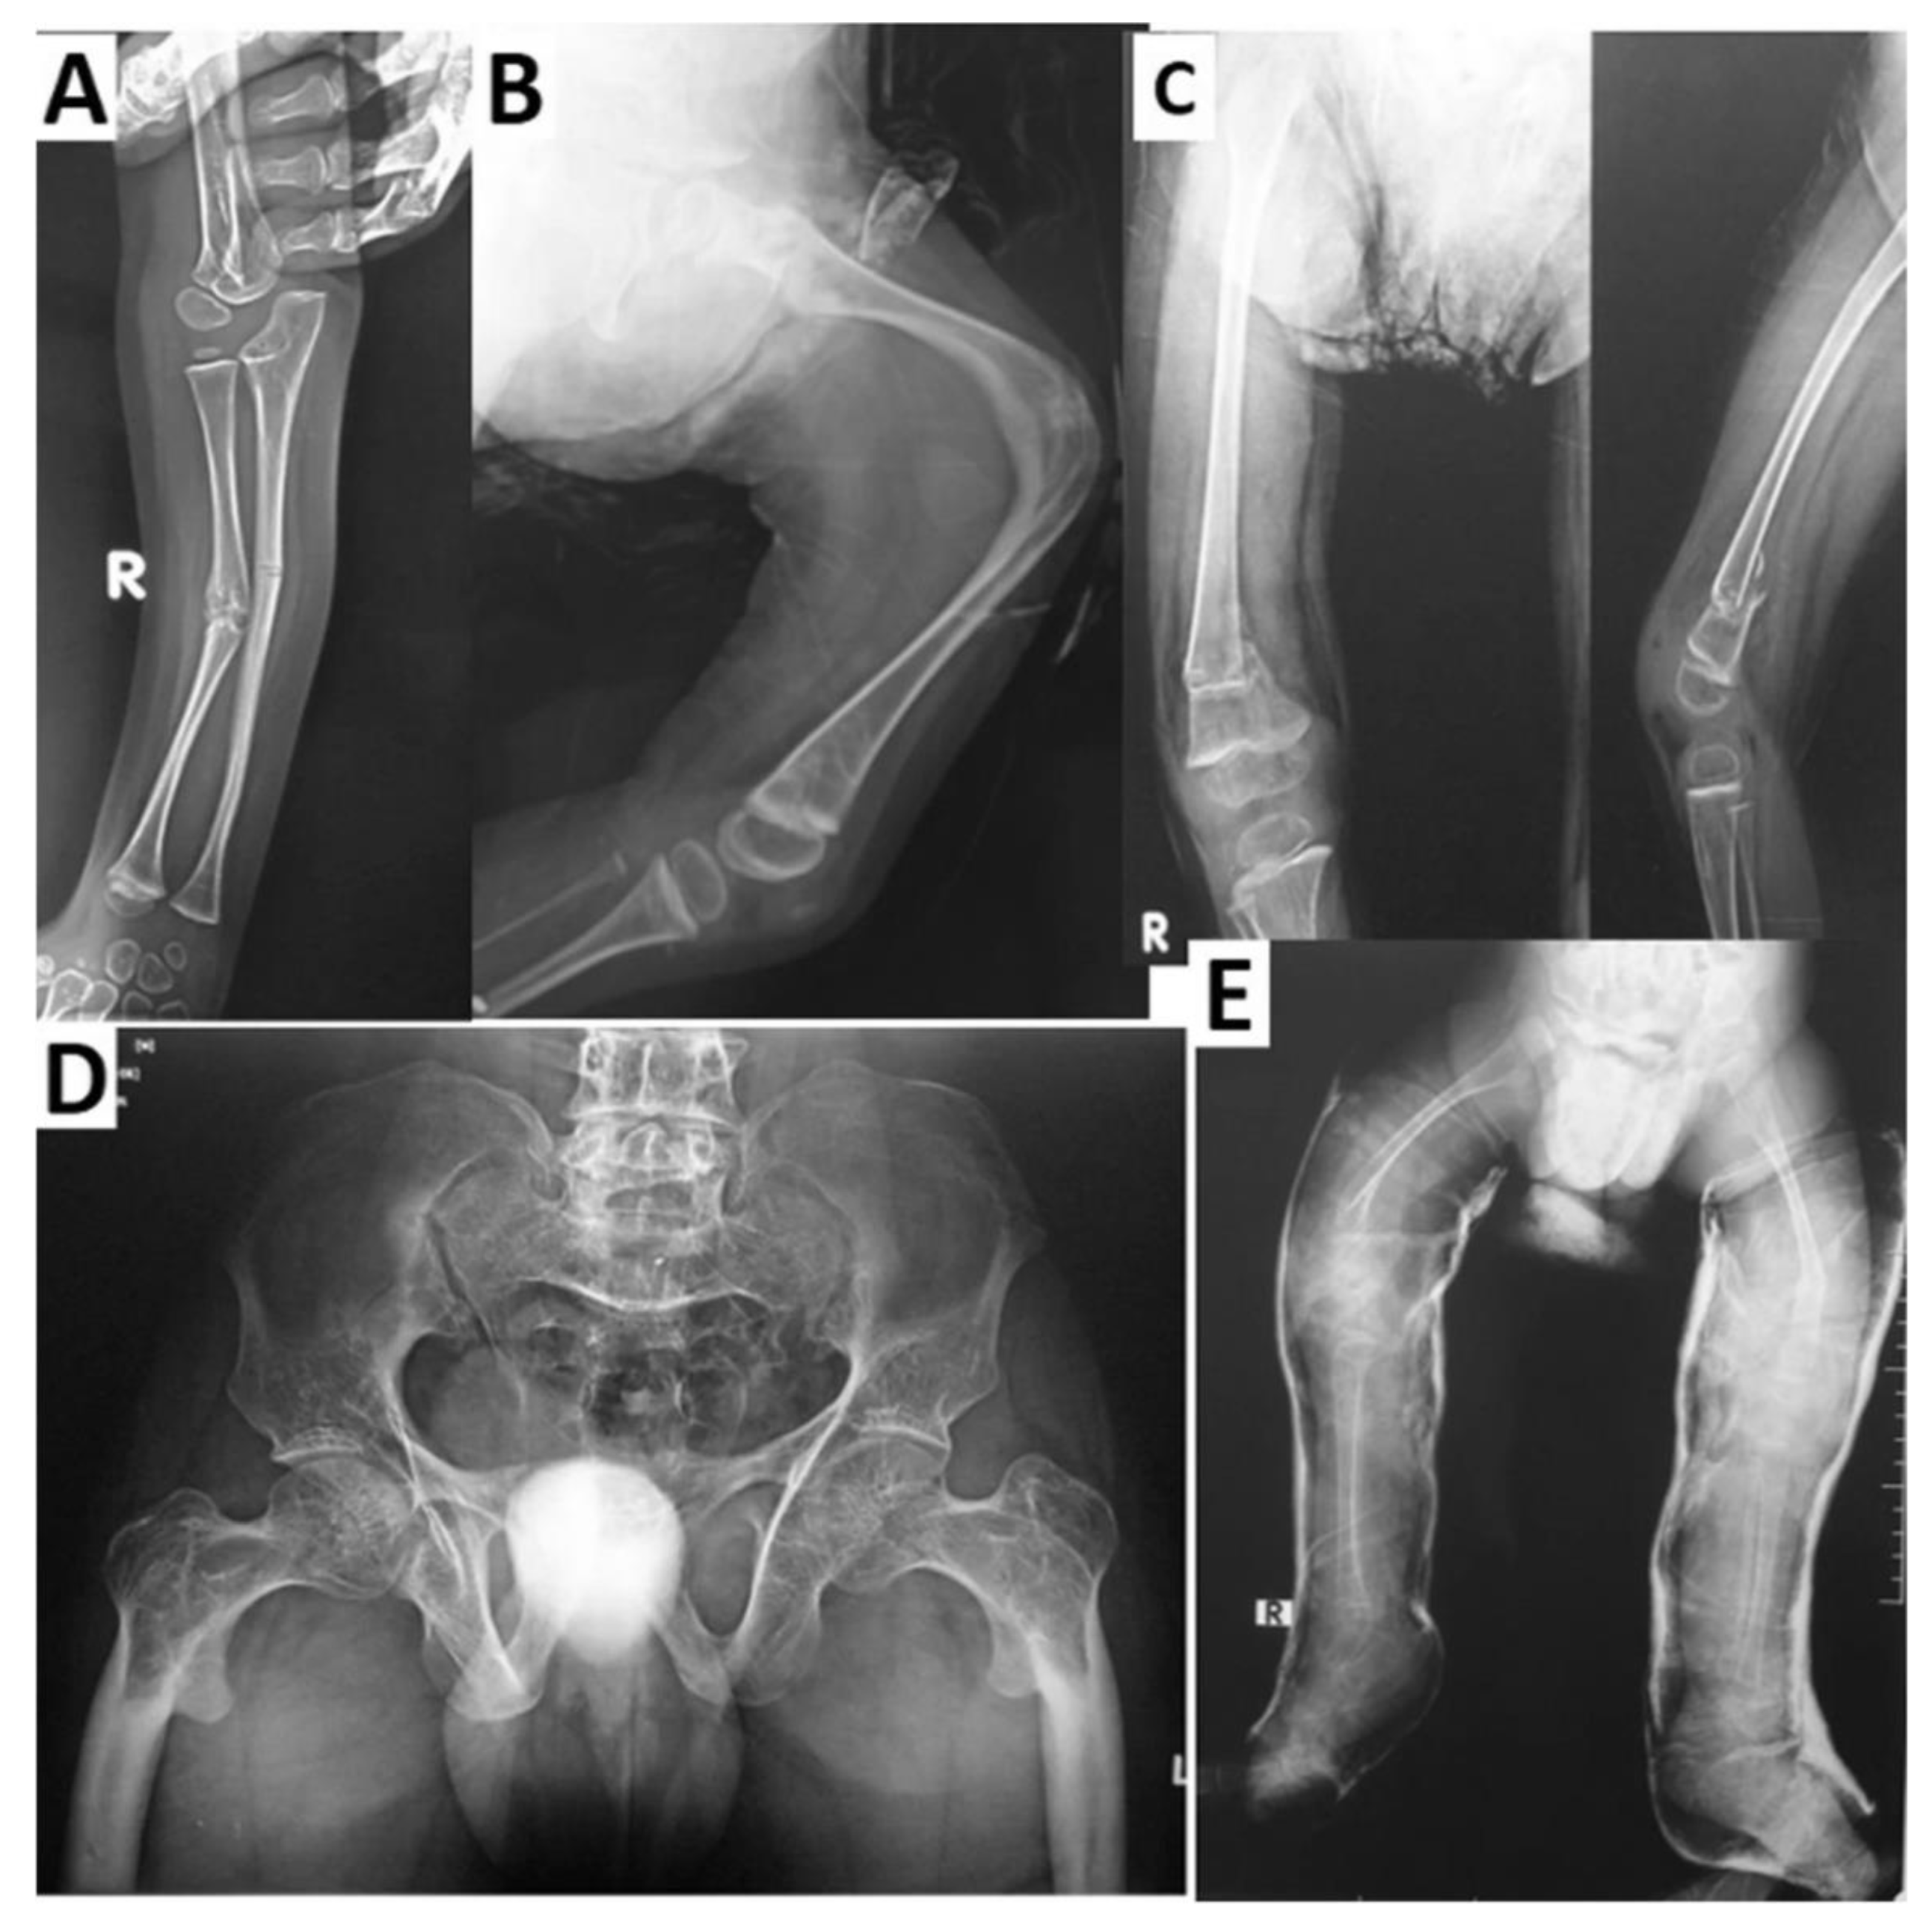

- Abdel-Hamid, M.S.; Elhossini, R.M.; Otaify, G.A.; Abdel-Ghafar, S.F.; Aglan, M.S. Osteoporosis-pseudoglioma syndrome in four new patients: Identification of two novel LRP5 variants and insights on patients’ management using bisphosphonates therapy. Osteoporos. Int. 2022, 33, 1501–1510. [Google Scholar] [CrossRef]

- Littman, J.; Phornphutkul, C.; Saade, C.; Katarincic, J.; Aaron, R. Osteoporosis, Fractures, and Blindness Due to a Missense Mutation in the LRP5 Receptor. Orthop. Res. Rev. 2023, 15, 39–45. [Google Scholar] [CrossRef] [PubMed]